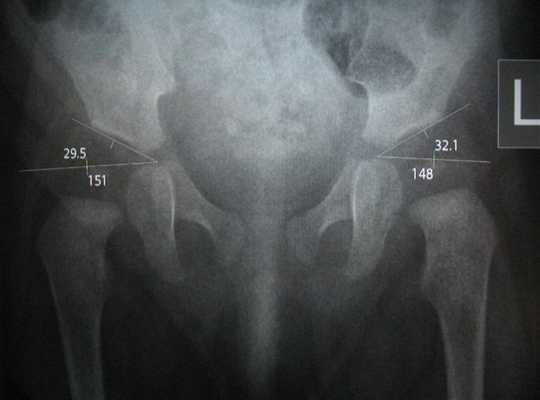

Учитывая угол Идельберга-Франка, угол Виберга и MZ-расстоянини децентрализации, статистическими методами можно выделить нормальные и патологические суставы: у взрослых значения тазобедренного сустава от 6 до 15 указывают на нормальную форму сустава; значения между 16 и 21 указывают на небольшую деформацию, а значения от 22 и выше указывают на серьезную деформацию, у детей значения от 15 и выше являются патологическими.

Также отмечаются смещение центра вертлужной впадины, уменьшение или увеличение шеечно-диафизарного угла (определяемого между вертикальными осями шейки бедренной кости и ее телом — диафизом).

Проводится измерение нескольких показателей в соответствии со схемой Хильгенрейнера (рис.4) [5, с.15-17]:

- величина ацетабулярного угла: это угол крыши вертлужной впадины, образованный в месте пересечения линии, проведенной через Y-образные хрящи, и касательной к верхнему краю вертлужной впадины. В норме у детей до 3х месяцев его величина находится между 30 о -20 о (значение в 20 о достигается примерно к 1 году)

- величина h: расстояние от горизонтальной линии Хильгенрейнера до наивысшей точки проксимального отдела бедра. В норме она симметрична с обеих сторон и примерно равна 9-12 мм. Свидетельством патологии является уменьшение этой величины

- величина d: расстояние от дна вертлужной впадины до величины h. В норме она также одинакова справа и слева и составляет не более 15 мм.